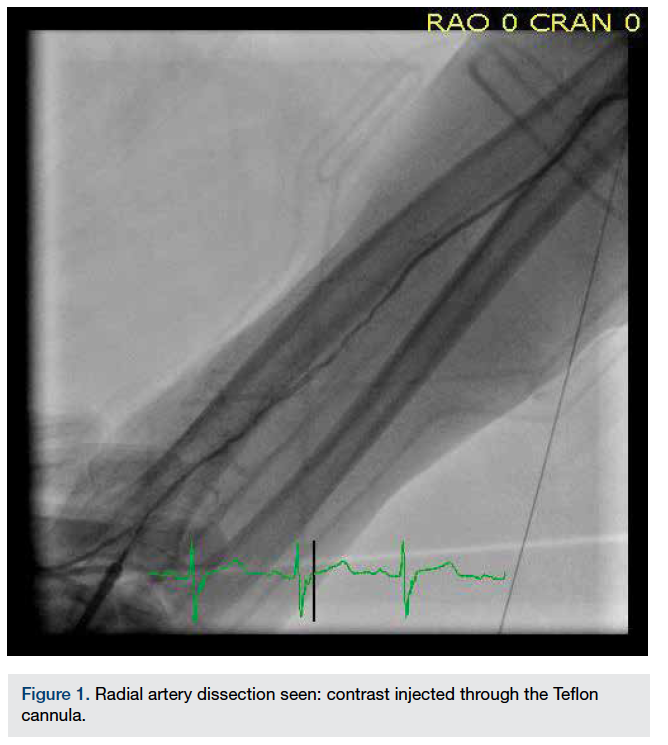

A 0.014-inch Prowater wire (Abbott Corporation) was given a 35- to 45-degree shape and was tactfully advanced into the RA. As the wire entered a side branch, it was reassuring that the wire was in the true lumen and unlikely to be in the false lumen. The wire was then advanced further through a tortuous course of the RA originating from the axillary artery (Figure 2).